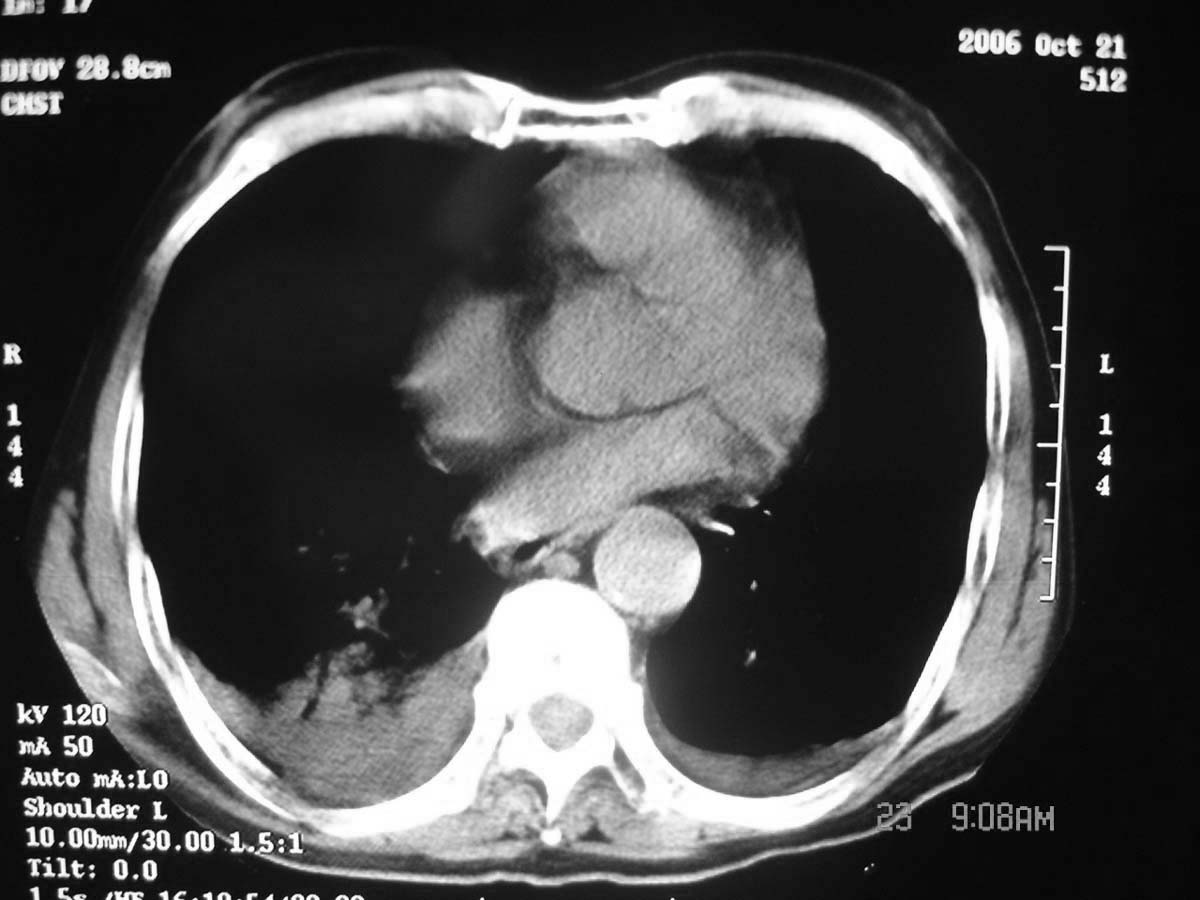

以下是引用守望可可西里在2006-11-23 14:33:00的发言:[br][br] 糖尿病病人很容易继发结核,病人又有双侧胸膜增厚、粘连、胸腔积液以及双上肺的斑片状、条索状影结核病灶影,以一元论考虑,右下肺病变首先考虑干酪性肺炎,可以正规抗炎治疗后复查,排除一般的肺炎。